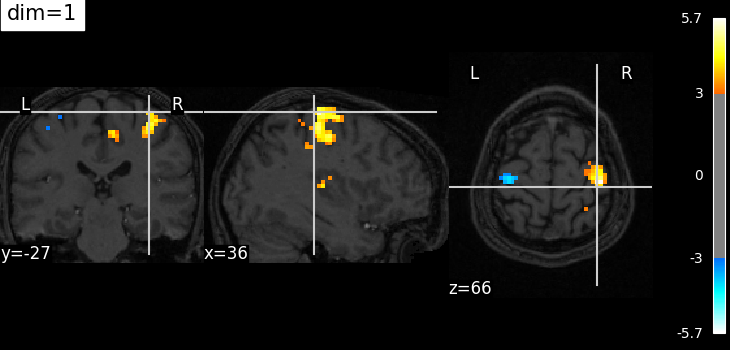

The dim argument controls the contrast of the background.

dim modifies the contrast of this image: dim=0 leaves the image unchanged, negative values of dim enhance it, and positive values decrease it (dim the background).

Plotting with more decrease in contrast with dim=1¶

plotting.plot_stat_map(

localizer_tmap_filename,

bg_img=localizer_anat_filename,

cut_coords=(36, -27, 66),

threshold=3,

title="dim=1",

dim=1,

)

plotting.show()